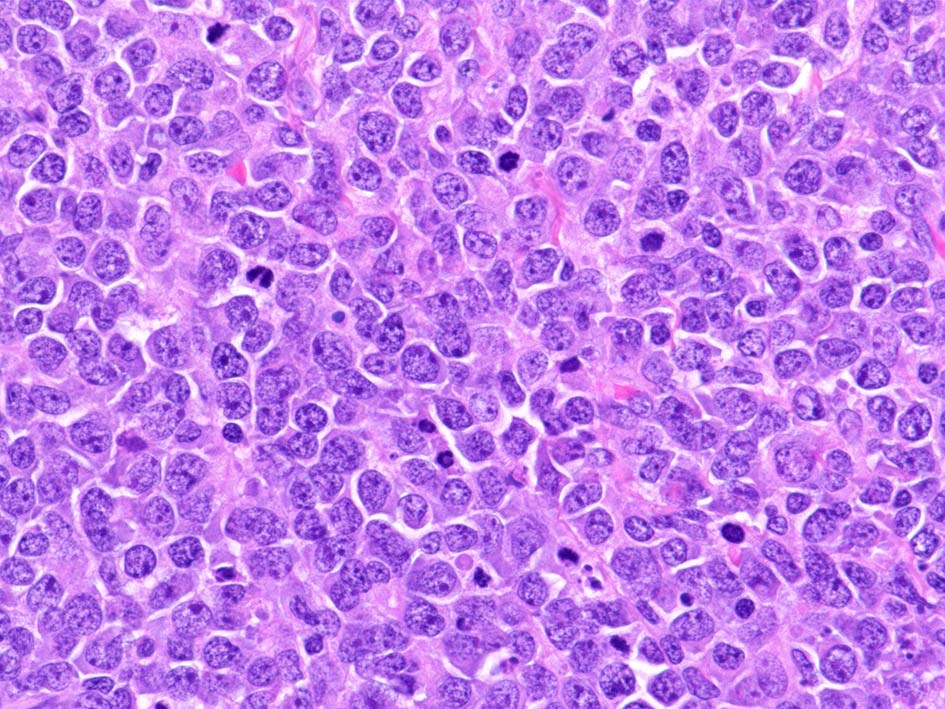

腫瘍細胞はcentroblastic cells. mitosisやapoptosisが多い.

小リンパ球と同程度か1.5倍くらいのサイズ, round/ convoluted nucleiをもつリンパ球がシート状密に増殖する. 核クロマチンは粗で, 核小体が認められる核もある.

DLBCLとは細胞の大きさや細胞所見が異なっている. 精細管への浸潤, 占拠所見がある.

類円形/多稜形の核をもつN/C比大の細胞. 粗大なクロマチンが増加, 核小体は不明瞭. DLBCLに認められるcentroblasts/ immunoblastsの細胞所見と異なる.